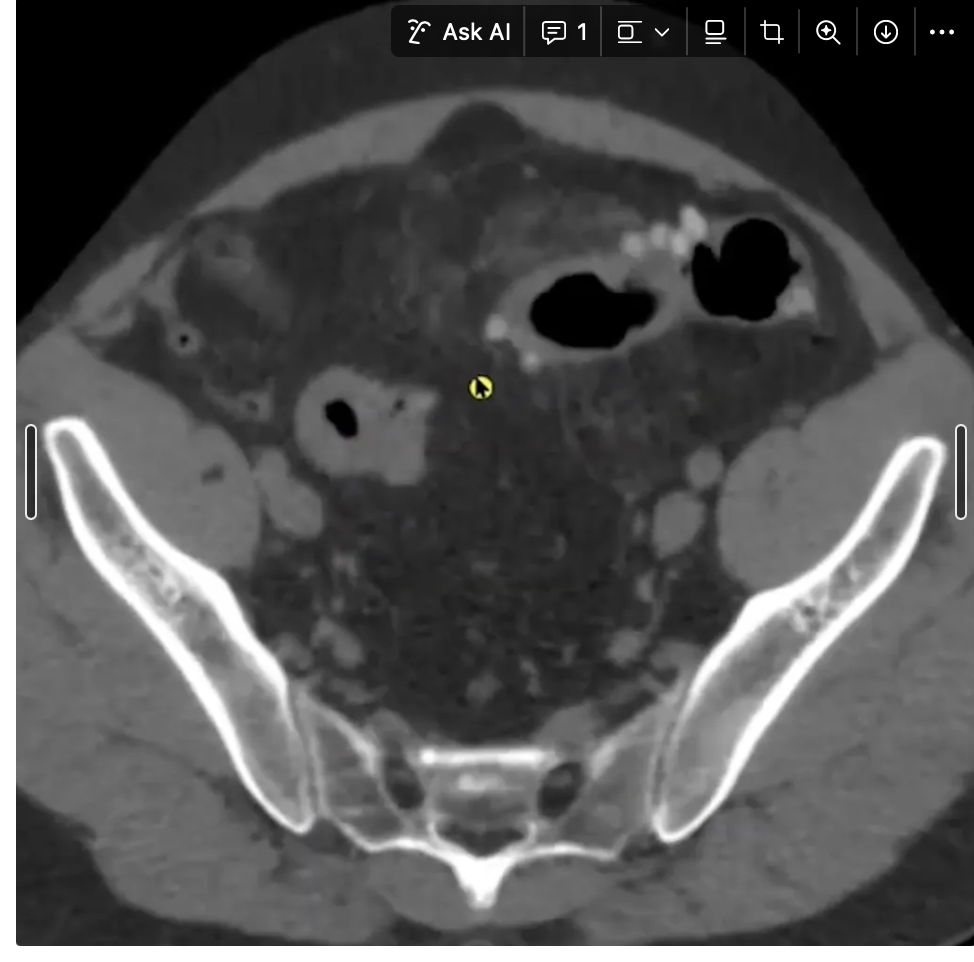

Achado?

A

DIVERTÍCULO COM AR DENTRO DELE EM CÓLON DE PAREDE ESPESSADA E BORRAMENTO DE GORDURA